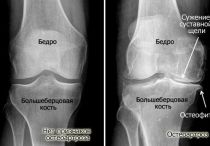

Корригирующая остеотомия: описание, особенности выполнения, возможные осложнения

Показания и противопоказания для выполнения корригирующей остеотомии. Хирургические техники. Осложнения после операции и реабилитация.